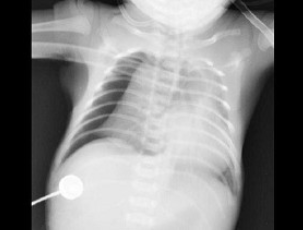

102、单项选择题

男,12天。呼吸困难,哭闹不止。X线检查如图,最可能的诊断为()

A.新生儿胸腔积液

B.新生儿心包积液

C.新生儿白肺

D.新生儿肺炎

E.新生儿气胸